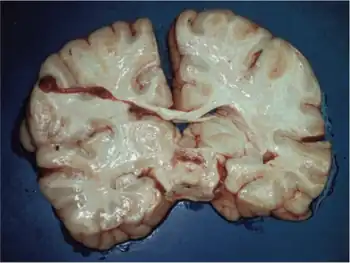

![]() | |

| Detection of numerous ragged red fibers in a muscle biopsy | |